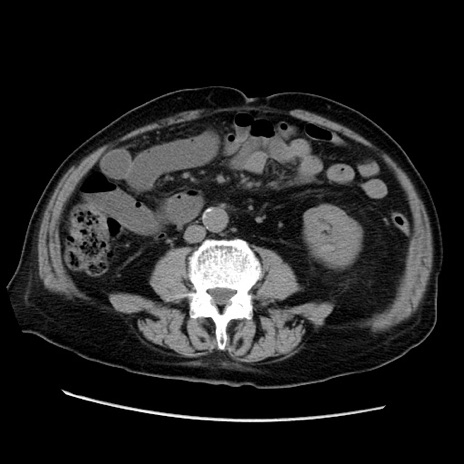

症例21(横断像)

【症例】70歳代男性

【主訴】腹痛

【現病歴】肝硬変・肝細胞癌にてかかりつけの方。約9時間前に食後より腹痛出現。症状が徐々に増悪し、嘔吐出現したため来院。

【既往歴】肝硬変、肝細胞癌(RFA、TACE後)

【身体所見】意識清明、表情苦悶様、BT 36℃、BP 129/78mmHg、P 88bpm、SpO2 97%(RA)、右上腹部から心窩部にかけて圧痛あり、反跳痛なし、筋性防御あり。

【データ】WBC 5800、CRP 0.16